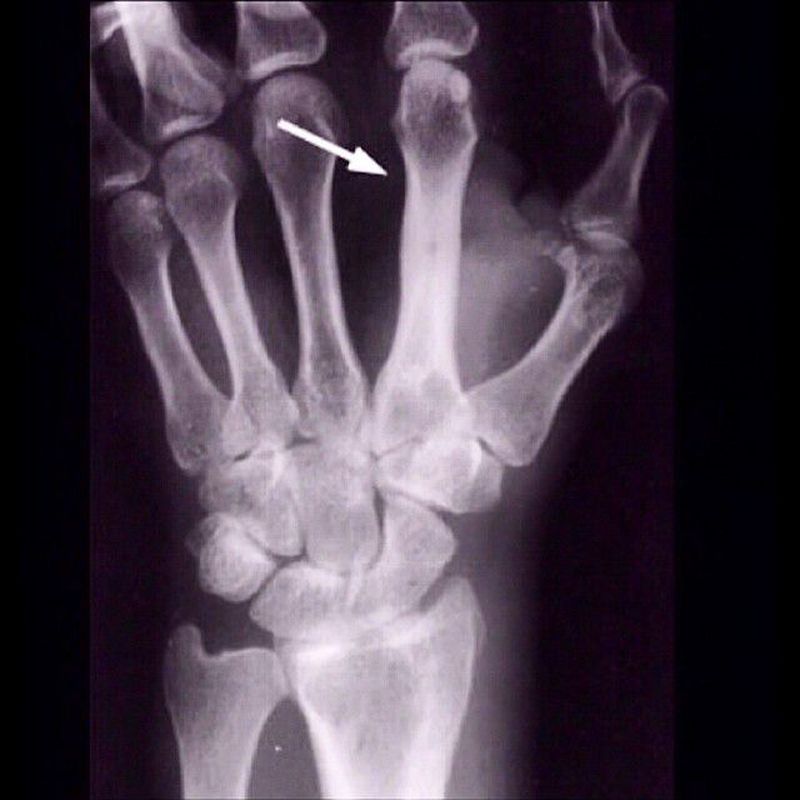

Plain-film radiograph showing osteomyelitis of the second metacarpal (arrow). Periosteal elevation, cortical disruption and medullary involvement are present. In general, osteomyelitis must extend at least 1 cm and compromise 30 to 50% of bone mineral content to produce noticeable changes in plain radiographs.Osteomyelitis means bone infection, mainly caused by bacteria (Staph aureus, E. Coli, etc).It can happen due to an injury to the bone (contagious osteomyelitis) or infection via bloodstream (hematogenous). The treatment of this condition depends on the severity, antibiotics are used in any case, and amputation done in rare cases if the blood supply to the bone is severely reduced.